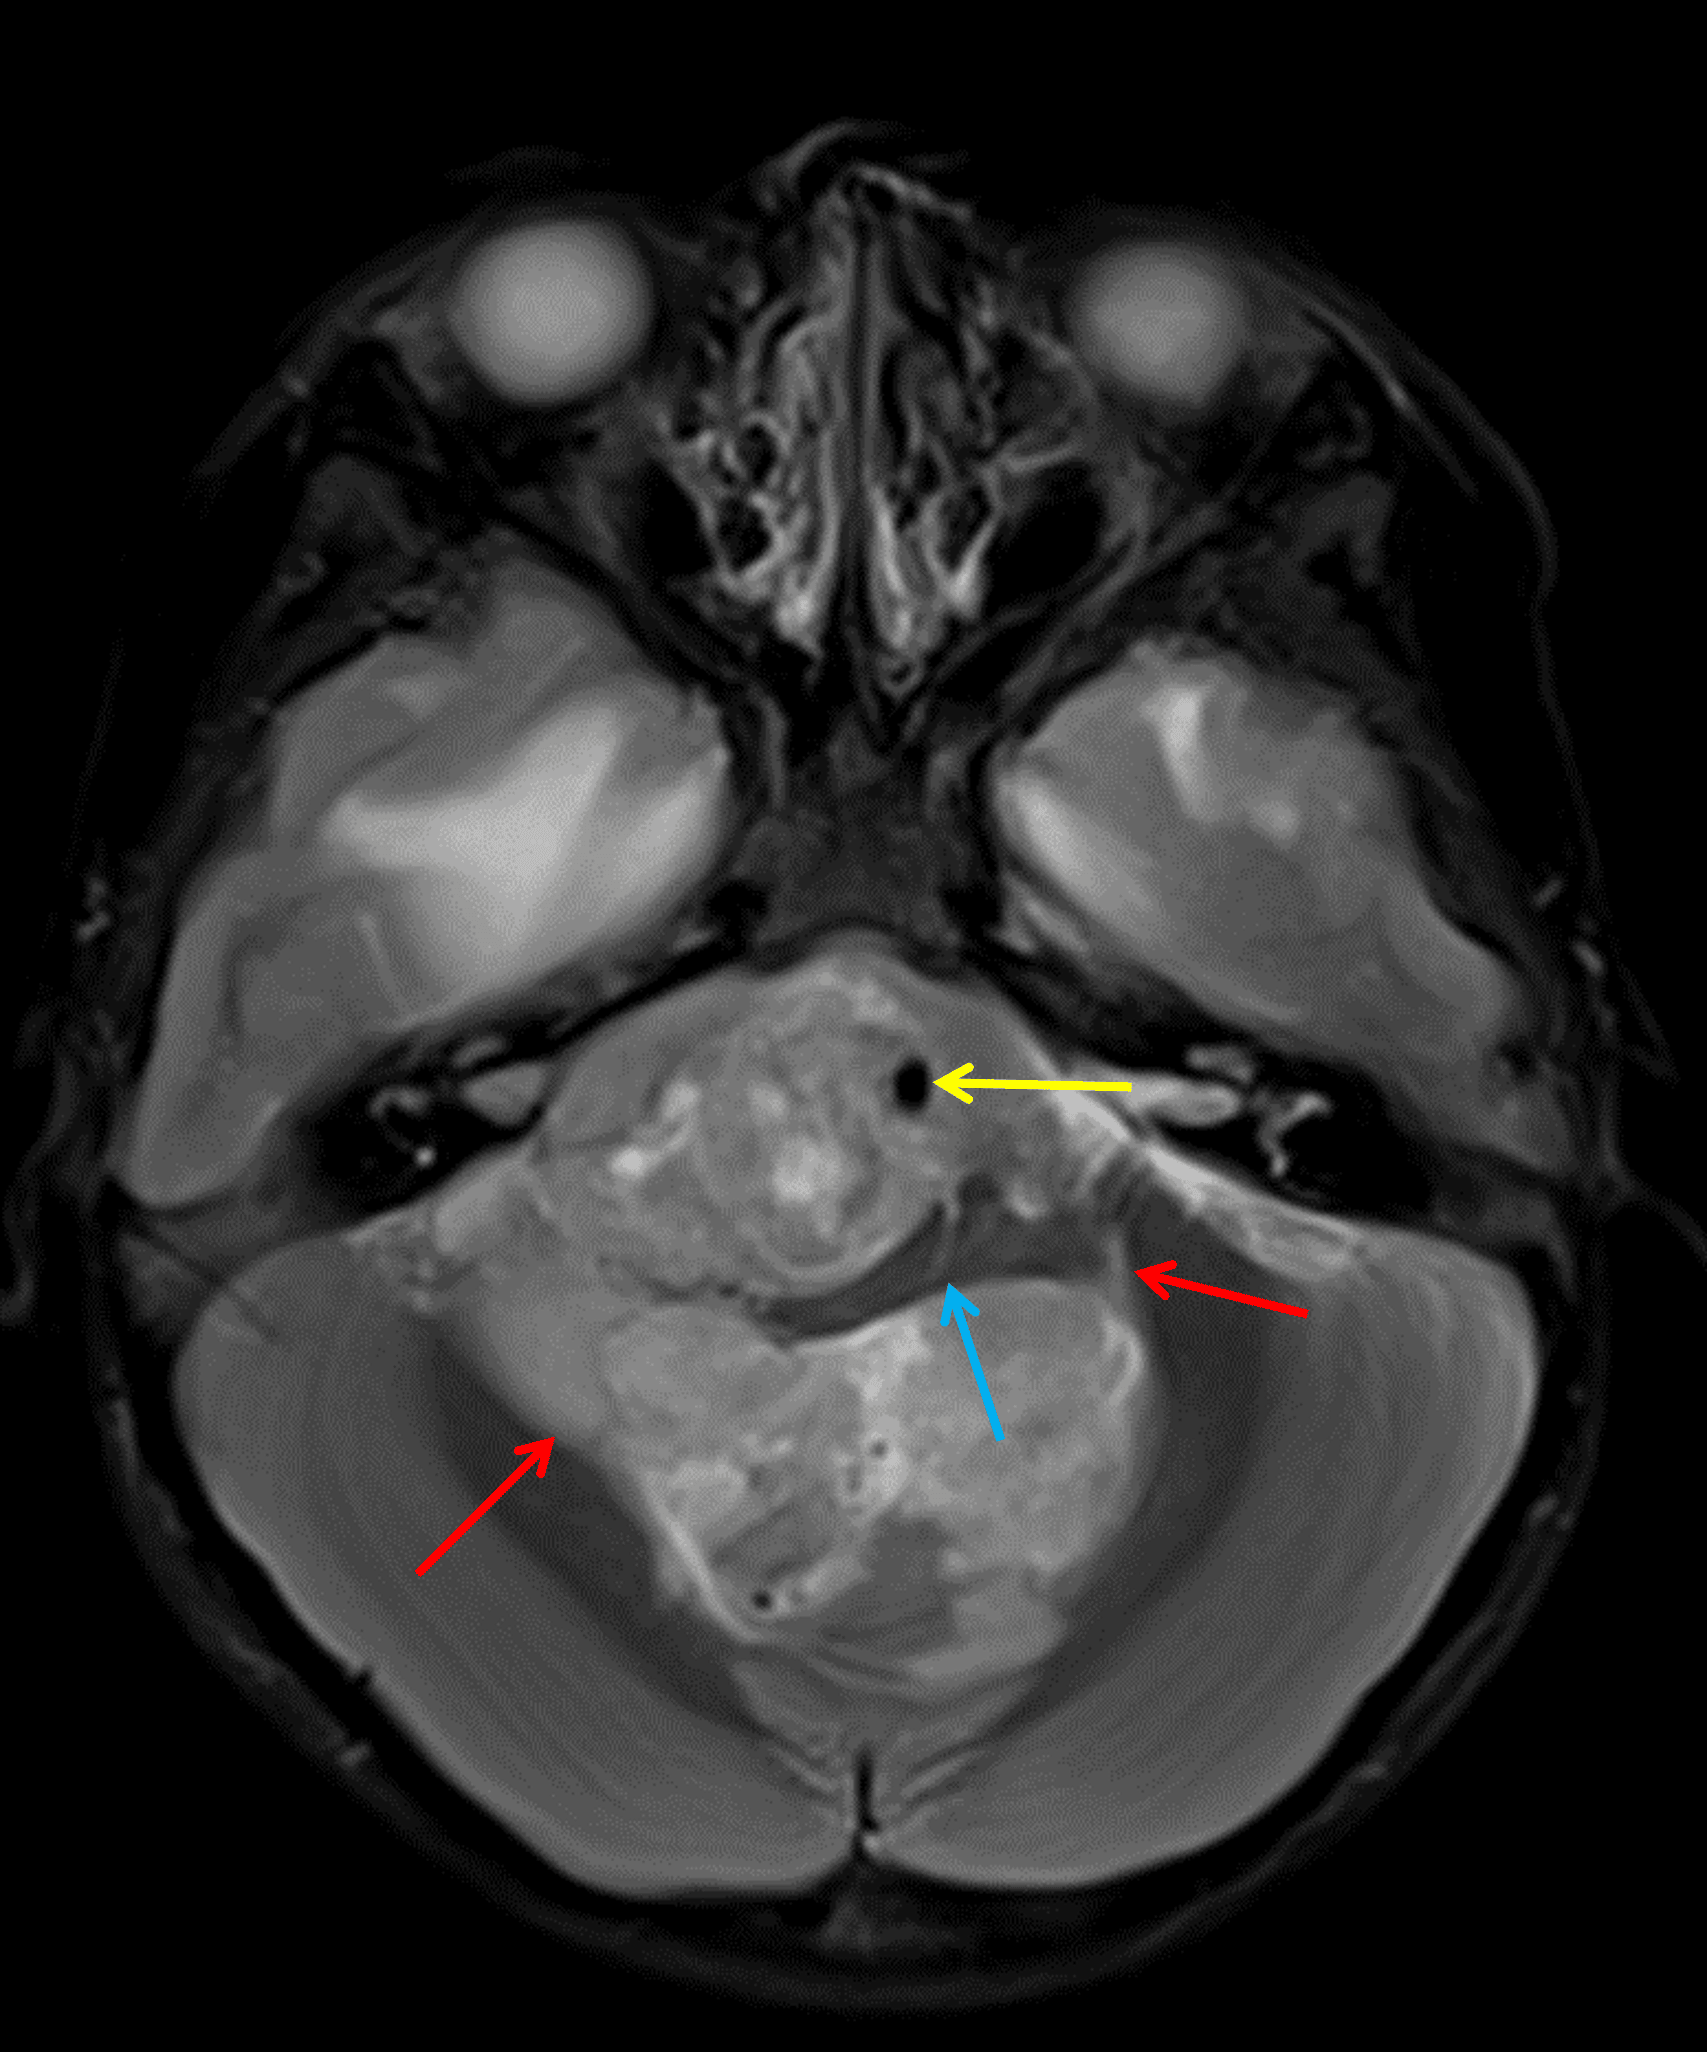

Posterior fossa ependymoma extending through the foramina of Luschka (red arrows), encasing the basilar artery (yellow arrow), and severely deforming the medulla (blue arrow).